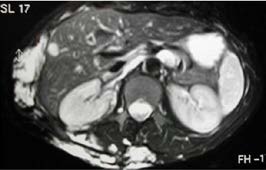

検査:診断には超音波検査(エコー)やMRI検査が重要です。MRIでは病変全体の形や広がりを確認でき、深部の病変の評価に優れています。

(写真:Cordisco MR, Vascular Anomalies in Childhood)